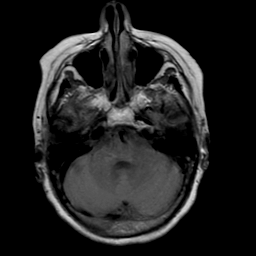

Stroke: proton density-weighted MR #2 -- Slice #5

[Home][Help][Clinical] Slice 5